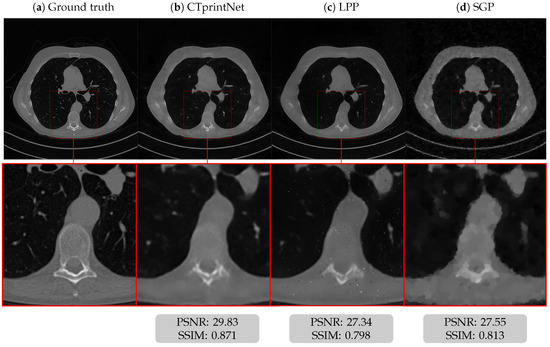

5.1. Results on a Synthetic Dataset

5.3. Results on a Realistic Dataset